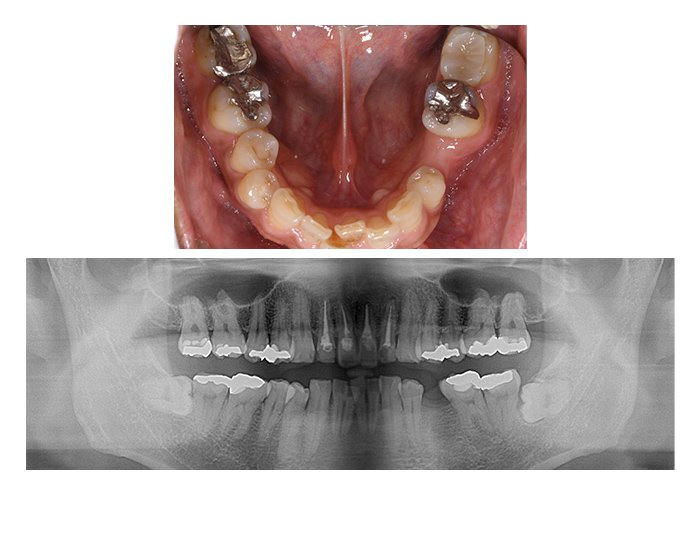

症例01 奥歯のインプラント

(女性、期間4カ月)

BEFORE(術前)

AFTER(術後)